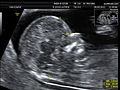

“Độ mờ da gáy” là xét nghiệm siêu âm để đo lớp dịch sau gáy thai nhi nhằm phát hiện dị tật.

Cô ấy đã thực hiện siêu âm đo độ mờ da gáy.

She had a nuchal translucency scan.